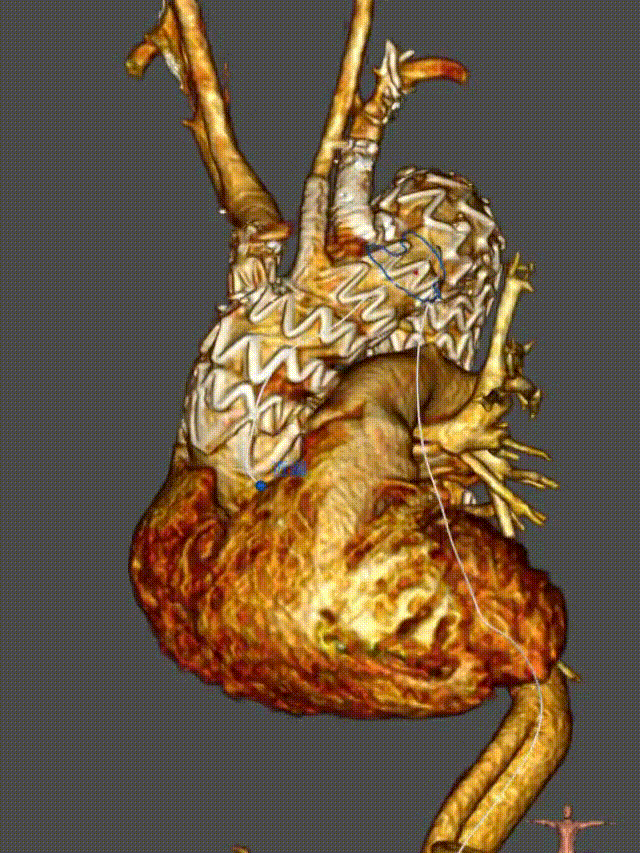

First-In-Human研究结果

★患者数据

纳入2022.12月-2023.8月长海医院11例男性患者(平均年龄63.2岁),其中动脉瘤64%(7例)、夹层36%(4例)。

★ 手术效果

技术成功率100%,平均手术时间153分钟(70-190分钟)

术后并发症:无卒中、截瘫、分支闭塞、逆撕性主动脉夹层发生,1例轻微内漏(I型),未干预。

★随访

术后12个月CT血管造影(CTA)随访显示,支架移植物位置稳定,无明显移位或变形,分支血管通畅。

First-In-HuMan study--CTA

CTA 12 monthes FU